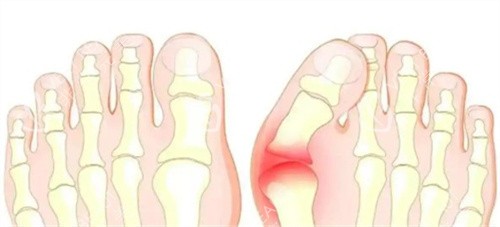

第四个原因:力线没调对,走路 “用错劲儿”

拇外翻手术的关键是把脚趾的力线调正,要是术后力线没调好,比如脚趾还是有点歪,走路时受力就会不均匀。

长期 “用错劲儿”,脚趾肌肉就会疲劳,自然又无力又疼。

自查方法:光脚站在镜子前,看看手术的脚趾是不是跟其他脚趾在一条直线上,有没有往外侧歪 —— 要是明显歪着,可能是力线的问题。